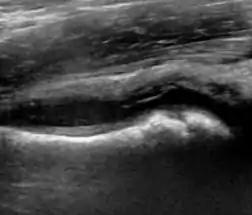

Figure 11:

Useful ultrasound measures in neonatal hip sonography, alpha and beta angles.[1]

Measurement of femoral head coverage.[1]